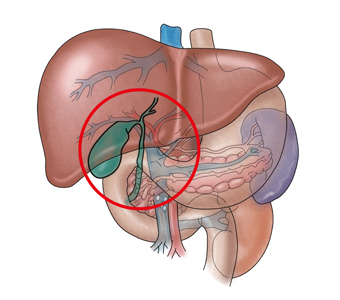

담낭암은 담낭(쓸개)에서 생기는 암입니다. 담낭세포에서 발생하는 선암종이 거의 대부분을 차지합니다. 따라서 보통 담낭암이라고 하면 담낭 선암종을 말합니다.

담낭암의 주요 원인은 담석과 용종으로 여겨집니다. 이형성-암 연쇄 과정의 주원인이 만성 염증이며, 이를 유발하는 주요 원인이 담석이라는 점에서 담석은 담낭암의 가장 중요한 위험 인자입니다. 특히 3cm 이상의 담석, 장기간 보유한 담석, 도재 담낭, 담석과 동반된 췌담관 합류 이상, 만성 장티푸스 보균자 등이 위험 인자로 여겨집니다. 또한 신생물성 용종이 담낭암과 관련될 가능성은 5~10% 정도인데, 크기가 1cm 이상인 경우, 50세 이상이면서 무경형 단일 용종인 경우, 담석이 동반된 경우 등이 위험 인자로 꼽힙니다.